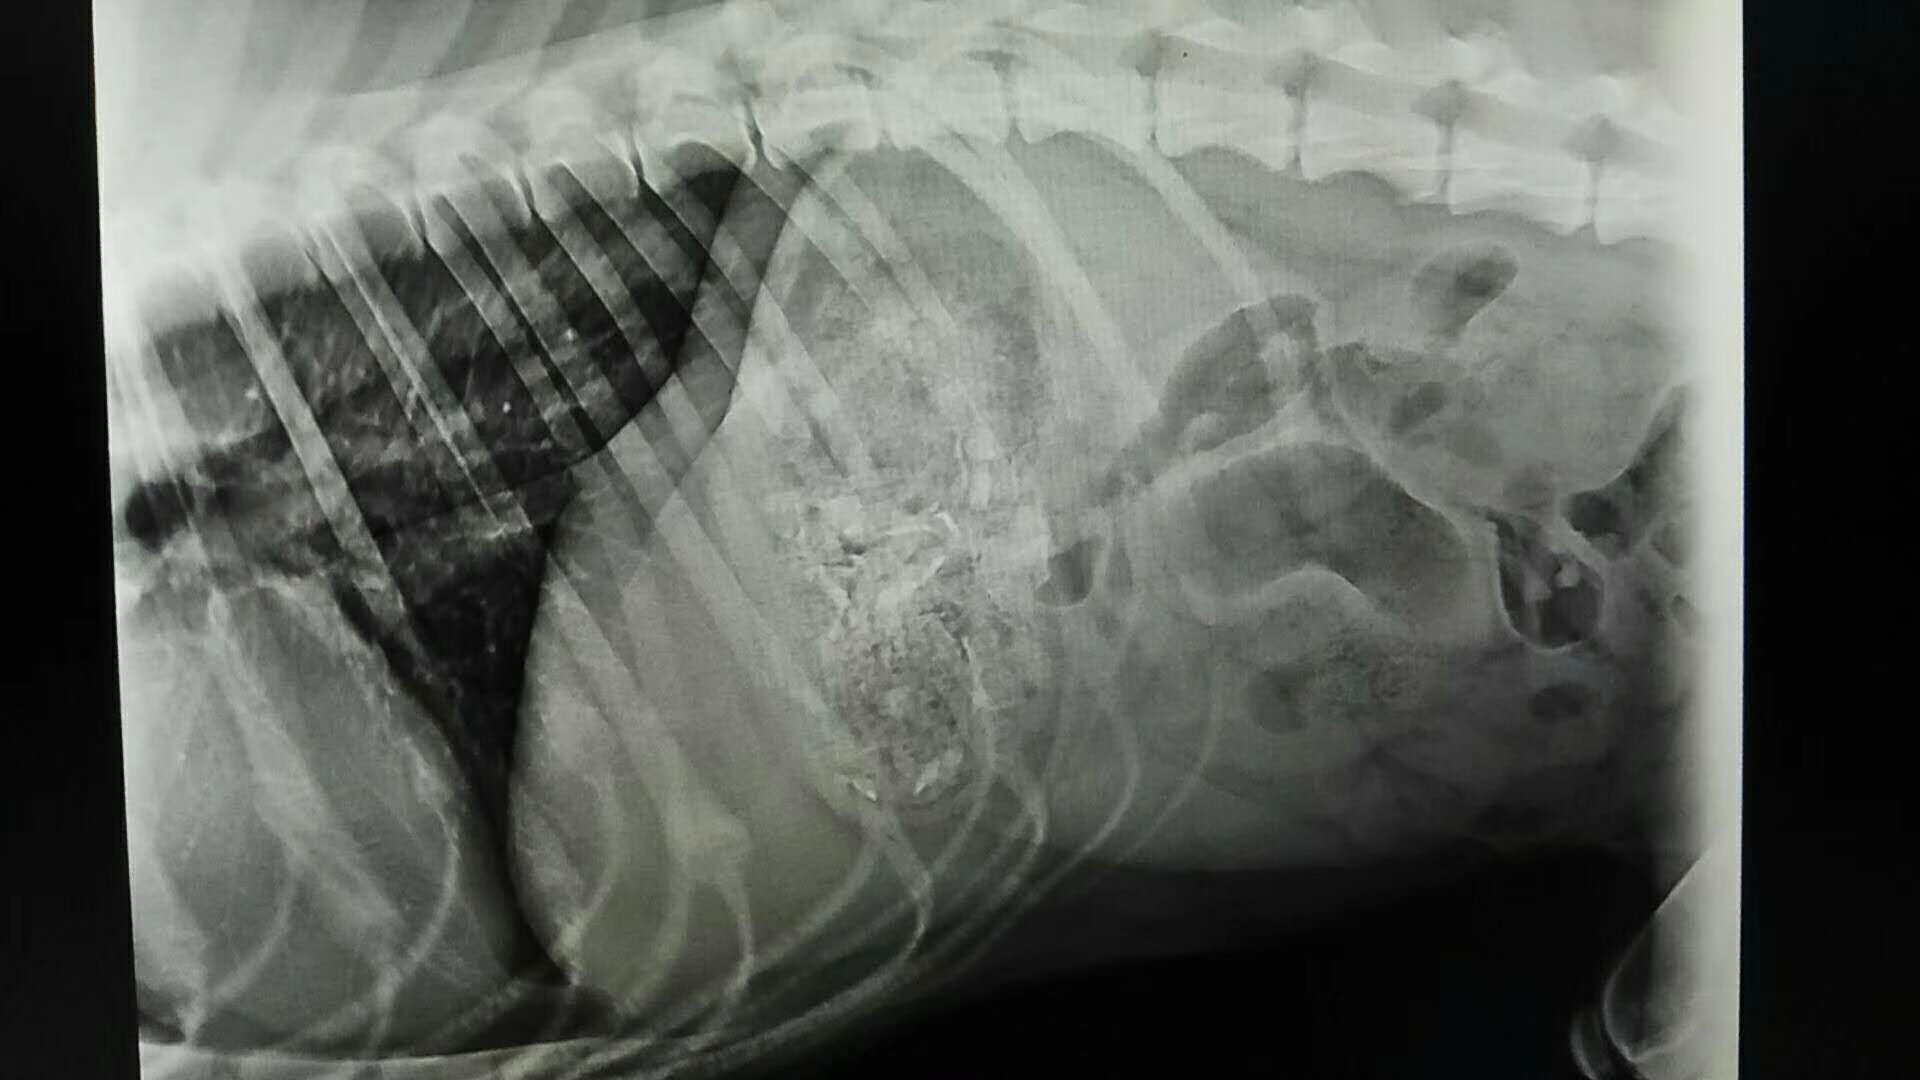

胃內(nèi)異物取出術(shù)一例:金毛,唐唐,1.5歲,平時(shí)有異食癖,喜食正常食物以外的東西,大約3-4天前,將自己洗澡用的毛巾吞入肚中,今天出現(xiàn)較高頻率嘔吐,帶醫(yī)院確診手術(shù),手術(shù)順利,住院護(hù)理中。